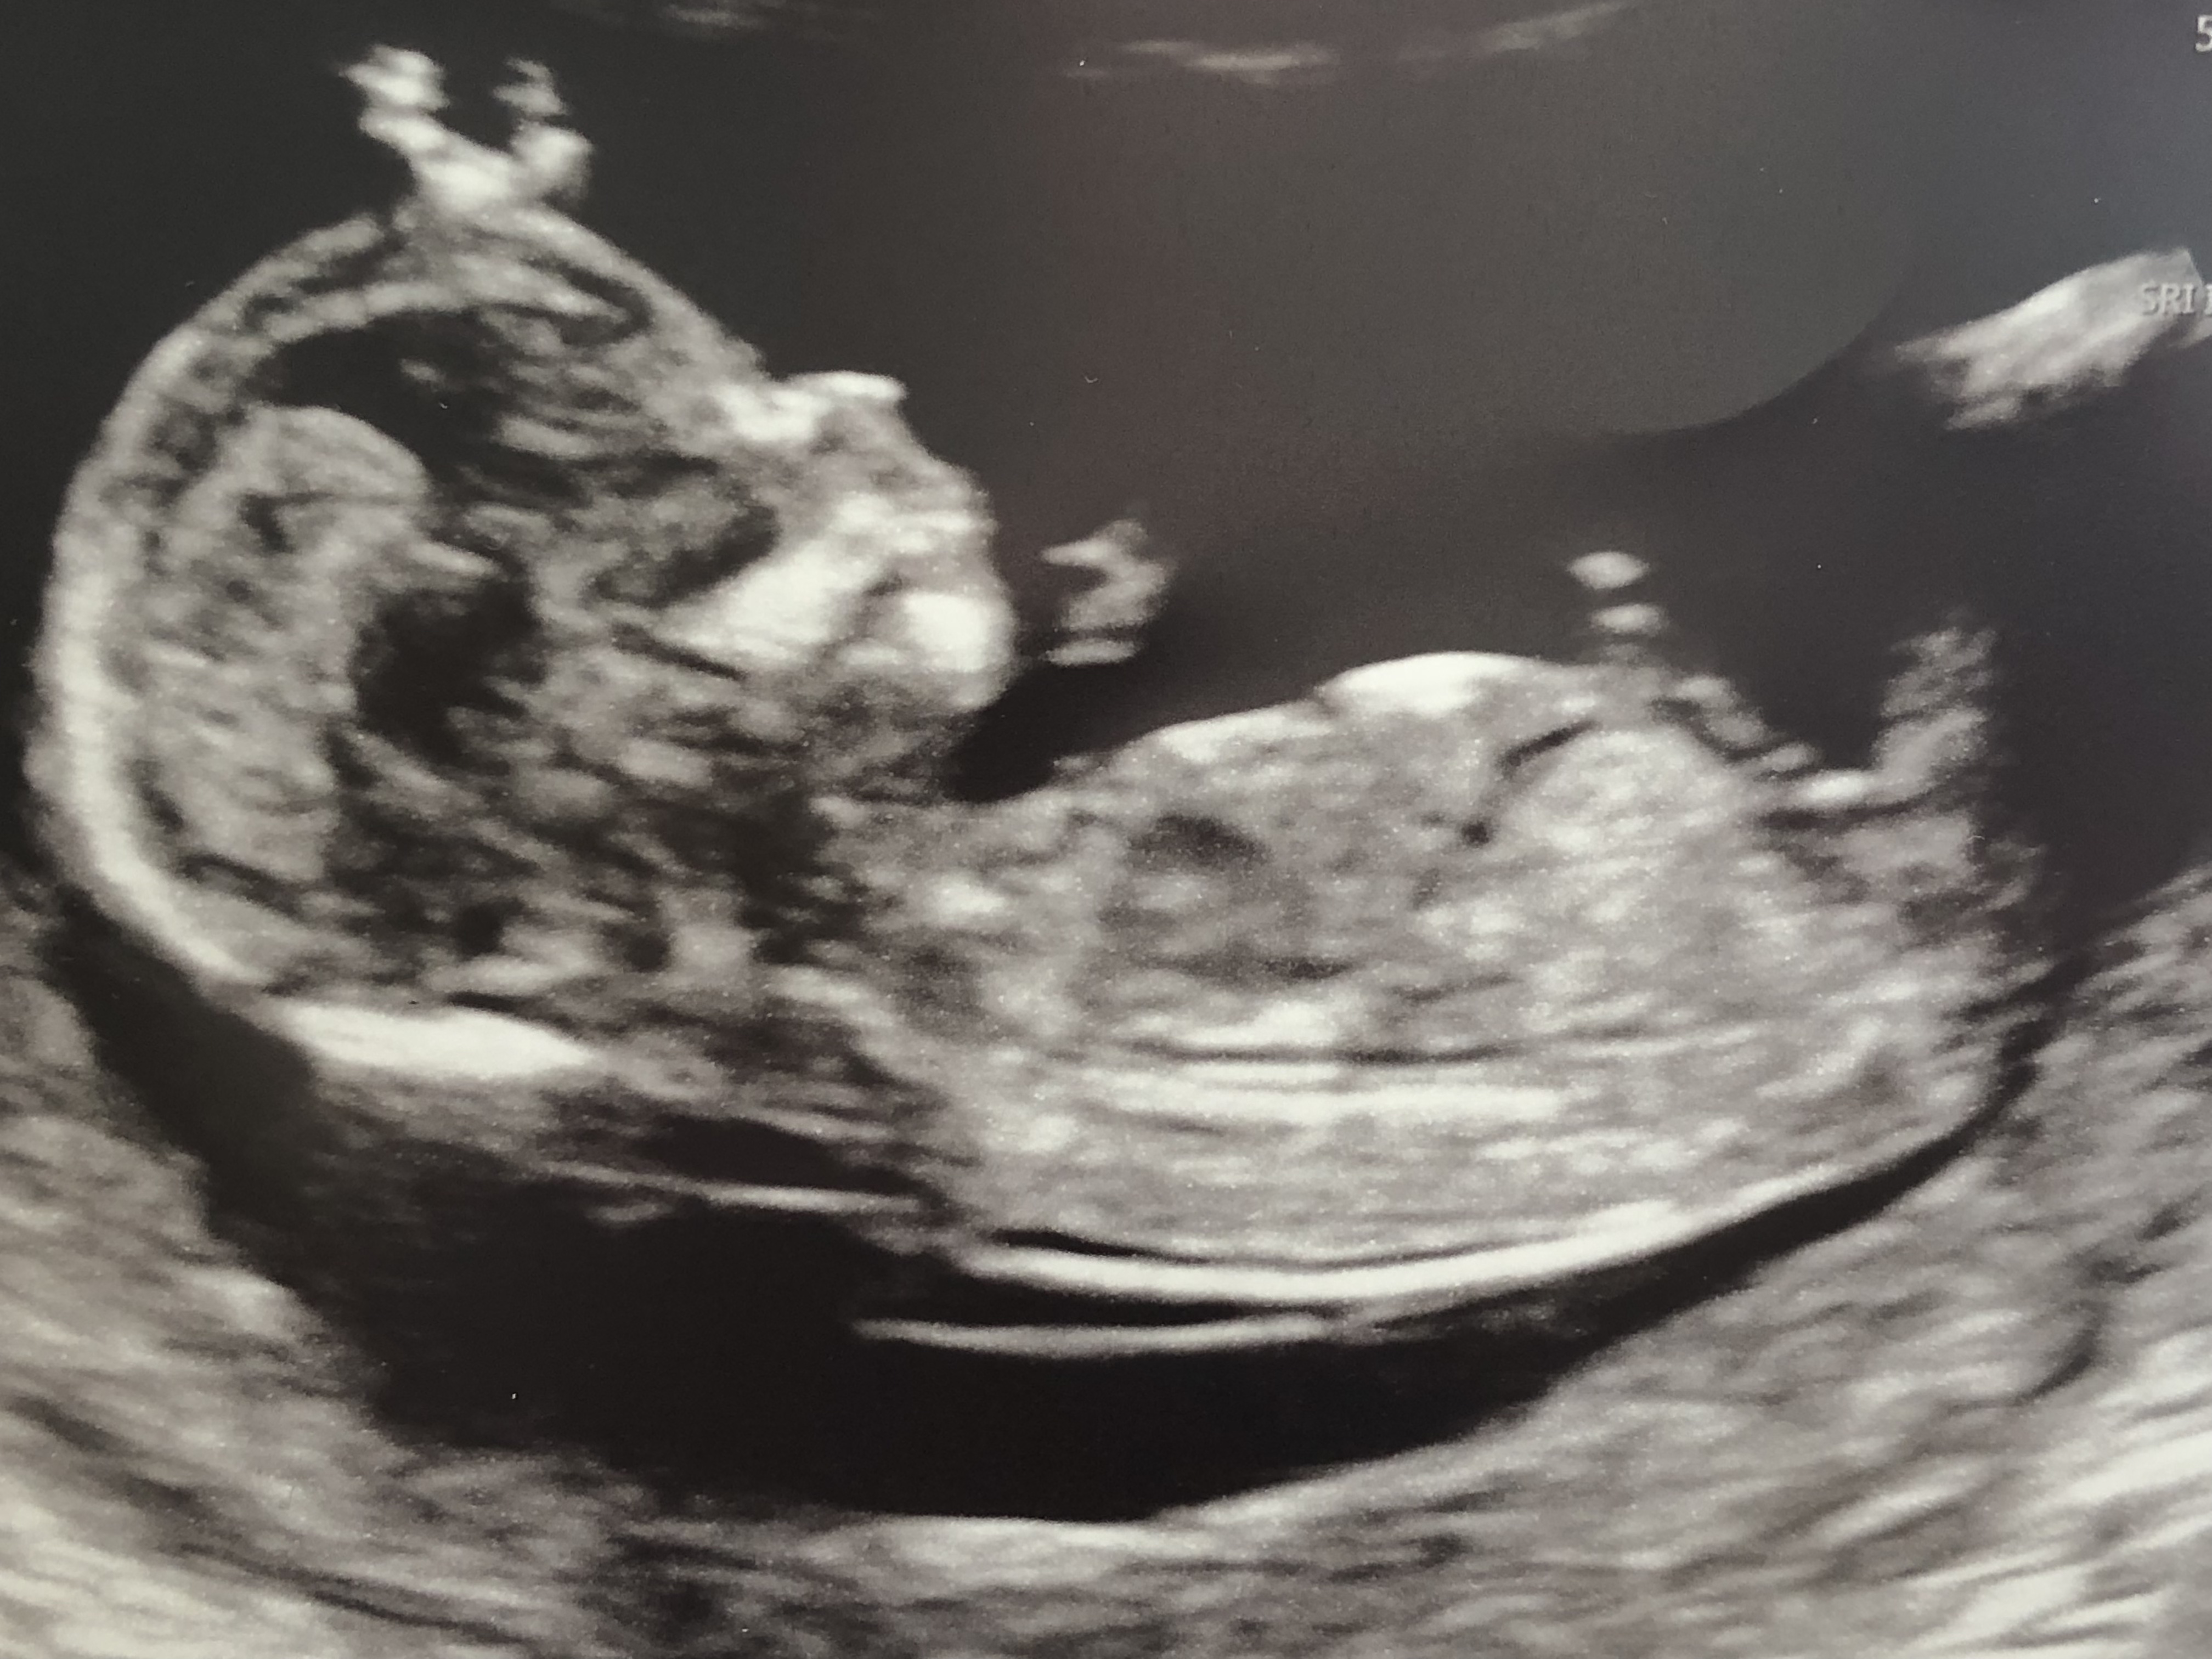

I’d really appreciated your gender guesses please...this pic is at 13 + 4